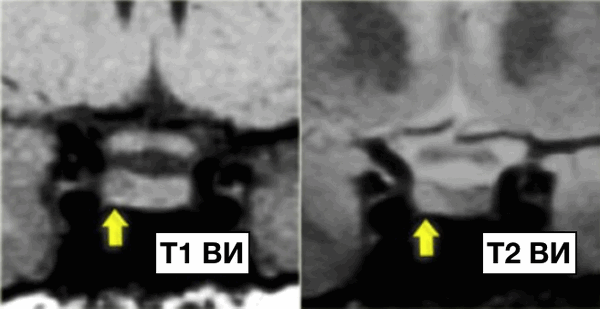

На данных изображениях представлен классический случай микроаденомы. На Т1 взвешенных изображениях в гипофизе визуализируется опухоль 3-4 мм в диаметре, незначительно гипоинтенсивнее по отношению к нормальной ткани гипофиза, а на Т2 взвешенных изображениях незначительное гиперинтенсивное.

Следовательно, дифференциальный диагноз выглядит следующим образом:

- микроаденома гипофиза

- киста карма Ратке

NB! Данные две патологии не всегда возможно отдифференцировать друг от друга.